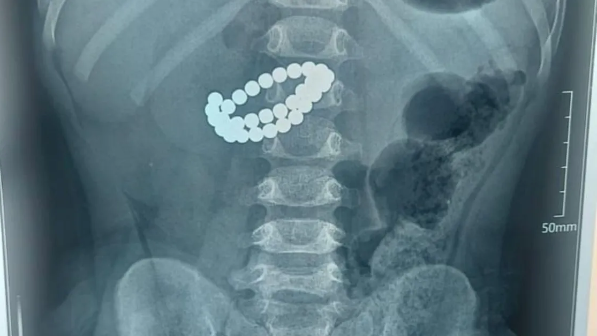

"Ота 4,5 сағатқа созылды": Екі жасар қыз 135 магниттік шар жұтып қойған

Өзбекстанда 135 магниттік шарды жұтып қойған екі жасар қызға күрделі ота жасалды, деп хабарлайды